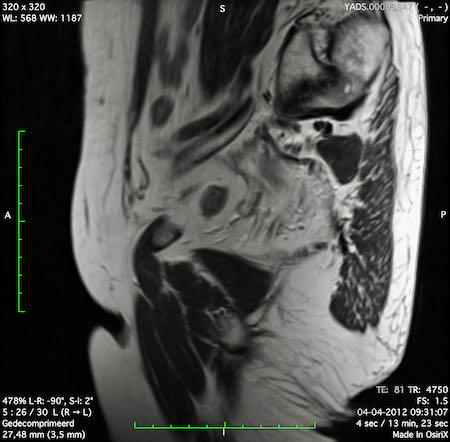

Hình ảnh

Các hình ảnh được cung cấp cho thấy ung thư biểu mô tế bào nhẫn với tình trạng dày lan tỏa thành trực tràng, hình ảnh bia bắn điển hình, và sự xâm lấn mỡ mạc treo trực tràng.